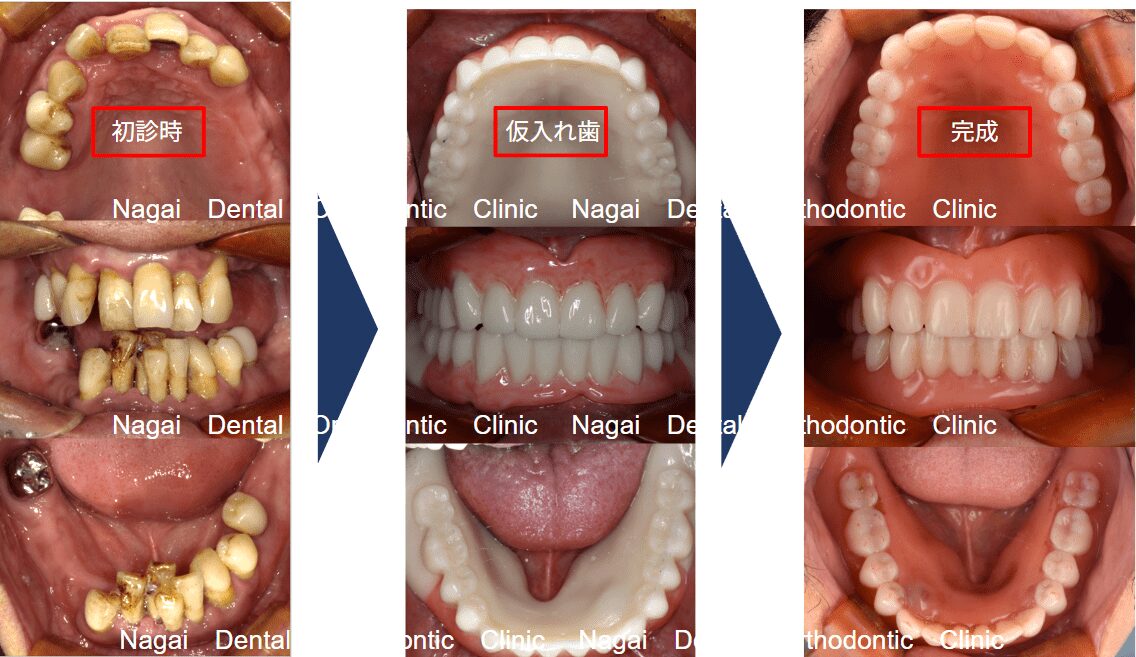

【口腔内の詳細変化】

▲崩壊していた咬合関係を根本から再構築しました

▲支持の安定が期待される治療を行いました

| 治療内容 | 上顎:ドイツ式入れ歯 |

|---|---|

| 年齢/性別 | 40代/男性 |

| 背景 | 重度歯周病と義歯の不適合により、歯列が乱れ、咬合(噛み合わせ)が著しく崩壊した状態で来院されました。当院では上下顎への精密なアプローチを選択し、不適合な義歯による粘膜の炎症や咀嚼困難を解消。崩壊していた咬合関係を根本から再構築しました。術後は、40代という年齢に相応しい健康的で美しい歯並びと、心地よく噛める機能を改善。審美・機能両面の回復により、生活の質が大きく向上しています。 |

| 治療期間 | 約1年(通院15回) |

| 費用 | 1,650,000円~4,950,000円(税込) |

| リスク/副作用 | インプラント手術は全身状態や持病によっては適応できない場合があります。また、術後の口腔清掃を怠ると、天然歯の歯周病に似たインプラント周囲炎が起こる可能性があるため、定期的なメンテナンスが必要です。 |